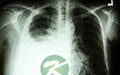

小编导读:胸腔积液又称为胸水,正常人胸膜腔内有3ml~15ml液体,但胸腔积液者体内液体量明显比正常人多。胸腔积液由肺感染、肺结核等感染性疾病、充血性心力衰竭等循环系统疾患、恶性肿瘤、肺梗阻、肝硬化、血管瘤破裂引起,临床表现为胸闷、发热、胸痛、脓胸。若胸腔积液量少,患者无明显临床症状,若胸腔积液量超过0.5升,患者临床症状会比较明显,出现症状时,应及早到医院就诊,并根据医生制定的治疗方案治疗疾病。胸腔积液怎么治疗?……

胸腔积液又称为胸水,正常人胸膜腔内有3ml~15ml液体,但胸腔积液者体内液体量明显比正常人多。胸腔积液由肺感染、肺结核等感染性疾病、充血性心力衰竭等循环系统疾患、恶性肿瘤、肺梗阻、肝硬化、血管瘤破裂引起,临床表现为胸闷、发热、胸痛、脓胸。若胸腔积液量少,患者无明显临床症状,若胸腔积液量超过0.5升,患者临床症状会比较明显,出现症状时,应及早到医院就诊,并根据医生制定的治疗方案治疗疾病。胸腔积液怎么治疗?